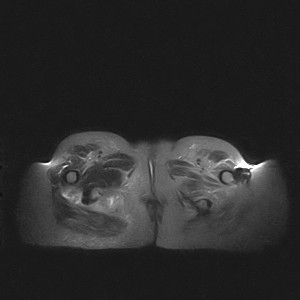

标题: MRI2691:读片病例2

我帮传的没看到病史!!!

图像太差了 1、右侧臀肌旁脓肿? 建议增强 2、左侧股骨头坏死并半脱位

1、左侧股骨头坏死并髋关节半脱位;

2、右侧臀肌感染,(可能褥疮所致)